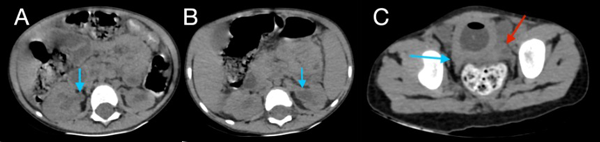

Figura 2. Tomografía de abdomen en ventana ósea, cortes axiales (A, B) y reconstrucción en 3D (C), donde se evidencia ausencia de unión de los elementos posteriores de L5 (flecha azul en A, flecha verde en C) y S1 (flecha azul en B y C) y ausencia de elementos sacro-coccígeos (flecha roja en C).

En este caso, se encontró una ausencia parcial sacro coxígea con preservación de S1 (Figura 1), asociada a no unión de elementos posteriores de L5 y S1 (Figura 2), siendo un síndrome de regresión caudal tipo I según Pang, asociado a alteraciones genitourinarias dadas por hidronefrosis bilateral (Figura 3) y engrosamiento de las paredes vesicales (Figura 4).